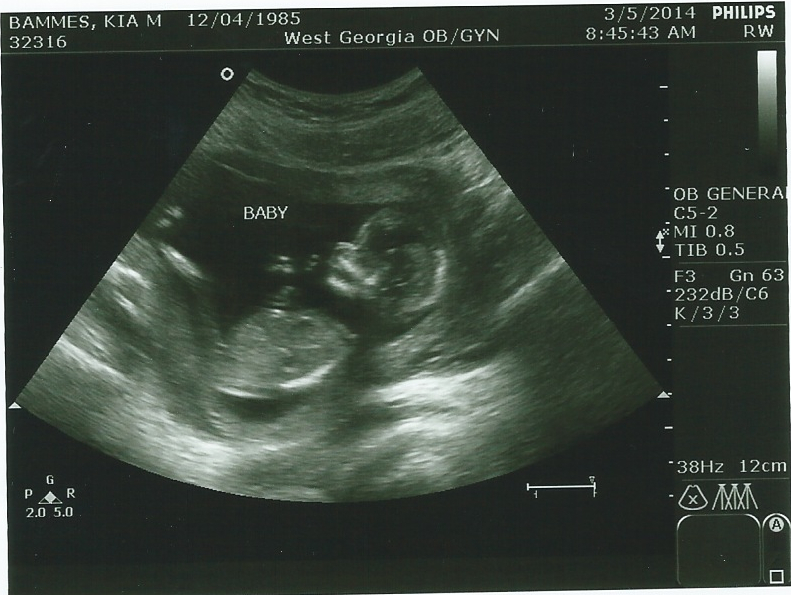

Ultrasound at 14 wks-B or G nub and skull guesses please!